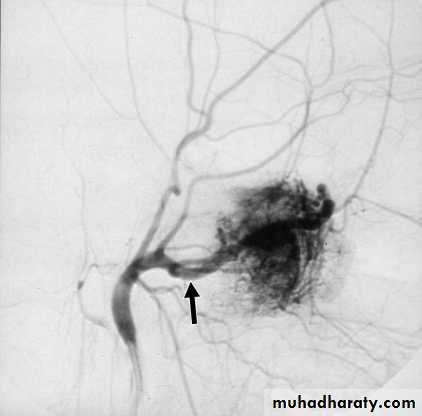

1. Imaging: a. X-ray of the base of the skull and a lateral view of the skull.

b. CAT scan, MRI and MRA.

c. External carotid arteriography.

2. Embolization is indicated preoperatively to control the vascularity of the tumour.